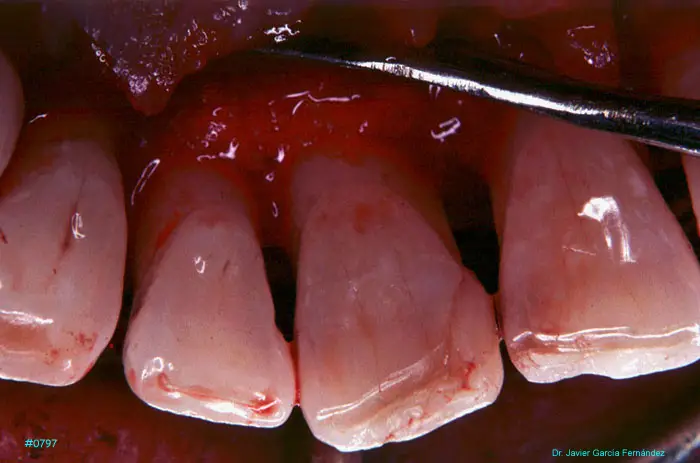

Atlas of Surgical Techniques in Periodontics. Chapter III. Atlas de Técnicas Quirúrgicas en Periodoncia